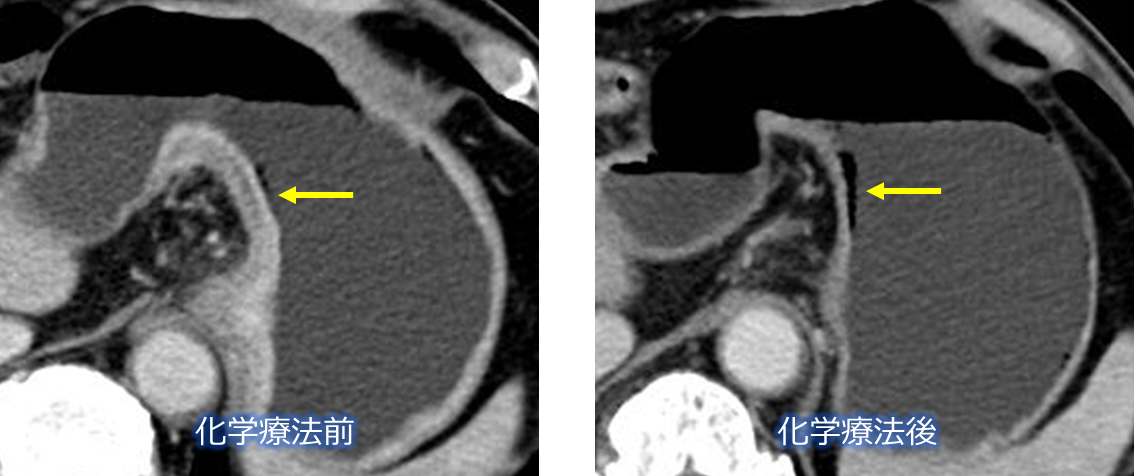

化学療法で消失したスキルス胃がん

化学療法で消失した大型胃がん